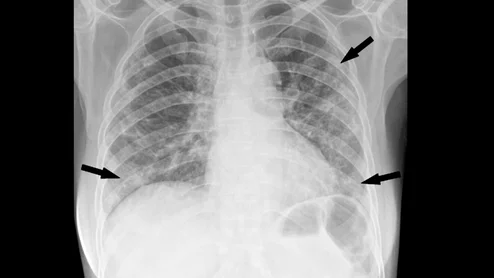

cvi42 | Plaque Circle Cardiovascular Imaging

The use of AI to evaluate plaque buildup in CCTA images has been one of cardiology’s biggest ongoing trends. Implementing this software into existing workflows, however, can be a challenge. An upcoming webinar is focused on providing guidance to hospitals and cardiology practices hoping to learn more about this topic.